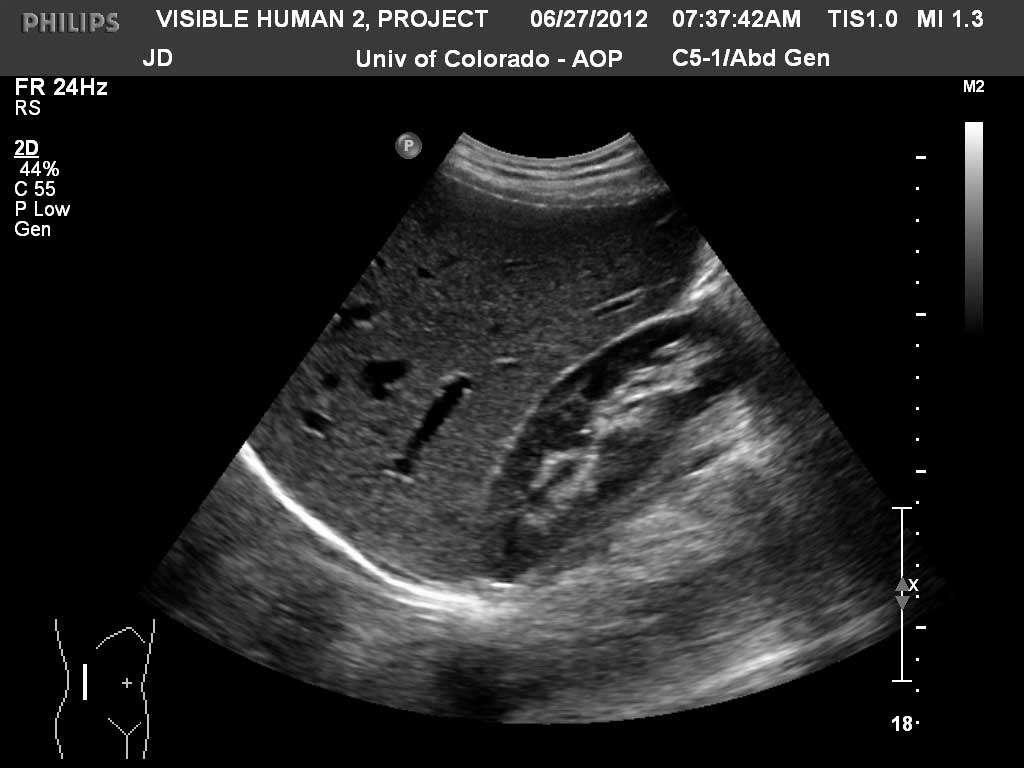

Long (Coronal) Liver and Right Kidney

Diaphragm

Liver

Kidney

Renal Cortex

Renal Sinus Fat

Right Hepatic Vein